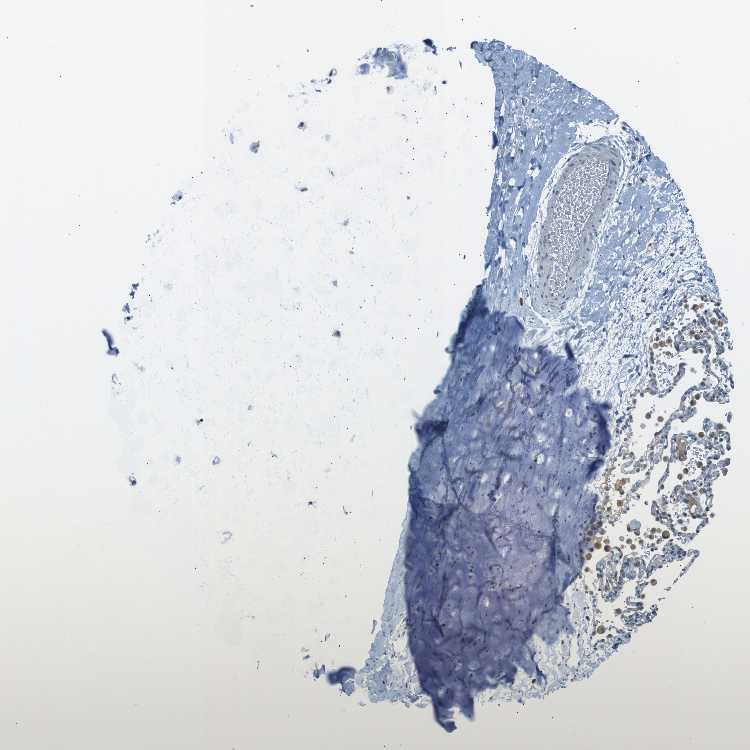

SOFT TISSUE 1 - Antibody stainingi

Antibody staining in the annotated cell types in the current human tissue is reported as not detected, low, medium, or high, based on conventional immunohistochemistry profiling in selected tissues. This score is based on the combination of the staining intensity and fraction of stained cells.

Each image is clickable and will lead to virtual microscopy that enables deeper exploration of all samples and also displays staining intensity scores, fraction scores and subcellular localization as well as patient and tissue information for each sample.

Antibody CAB016545

Chondrocytes Not detected

Fibroblasts Not detected

Peripheral nerve Not detected